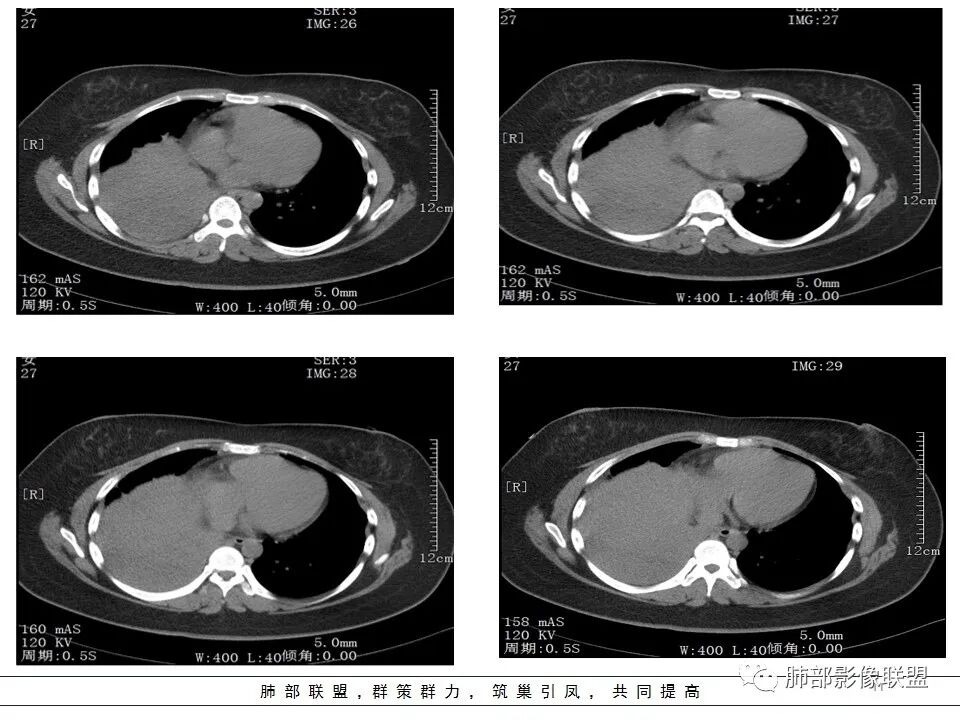

本病例特点是中叶病灶和下叶病灶不一样,支气管腔内的病灶又是怎么样的呢?我们要是有沿支气管重建的冠状位、矢状位会更有利于分析。第一,中叶病灶明显粘液样改变、低密度,且低密度区有占位效应、膨隆,确实要考虑粘液表皮样癌。第二,中叶和下叶支气管显示不出来,但血管显示出来了。中叶病灶血管稀疏、细小,下叶病灶血管粗大、走形正常。朝外肺不张实变,不是单纯的肺不张,肺不张一般体积明显缩小、血管聚拢,该病例肿瘤于其中成分不一样,所以上叶部分病灶考虑为下叶病灶占位效应及膈面向上推压引起,中叶萎缩。综合腔内堵塞、纵隔淋巴结肿大要考虑恶性。

支气管层面位置朝下强化明显,支气管腔内、远端是有差异的,腔内哪些是粘液?哪些是肺组织?是单纯实变?还是合并感染?还是外围都是病变?支气管腔内病变?

该病灶明显实变,需鉴别是内朝外,还是外朝内病变。该病灶内血管走形自然,肺门区血管无明显受压移位,且非起源于胸膜,不张肺组织或者不张肺组织夹杂炎性病变。而非典型肺炎型肺癌及外朝内的其他恶性病变。

内朝外病变是支气管腔内病变?还是支气管周围病变呢?如果支气管周围大恶性肿块灶,那其内血管也不应走形自然,应杂乱无章,所以只能是腔内病变引发支气管周围病变。

1.年轻女性,发热6天,咳嗽咳痰3天。高热伴腹泻。

2.右肺中下叶大片实性密度影,体积有缩小,密度不均,不均匀强化,前份可疑小范围液性密度区。

3.中间段支气管阻塞,腔内隐约见息肉样结节或突入,结节有较明显强化,这很重要,说明它有生命力,强烈提示新生物,而非分泌物或异物等等。

可惜腔内腔外混沌一片,我们不能分辨管壁及管壁外细节,我们不能判断新生物实际大小,不能判断局部支气管彻底破坏还是结节影跨越腔内外。

4.年轻、女性,支气管腔内相关新生物,会想到类癌或涎腺类肿瘤,如粘液表皮样癌等。强化较明显类癌可能性较大。支气管鳞癌和间叶组织肿瘤的可能性都非常小。

5.如此大范围实性密度影,结合高热临床表现,阻塞性肺炎诊断应当是成立的。病灶内梭形液性密度区,未见强化,符合炎性分泌物。